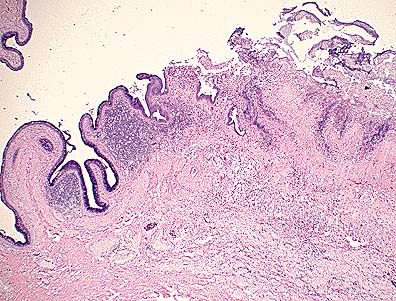

Numerous well-demarcated granulomas in the subcutis of the neck of an emu. (HE, 100X, 64K)

The section consisted of multiple lobular structures. Dense to myxomatous connective tissue separated individual lobules. A loose lipid and vacuolated reticular fibrinous material within which were numerous multinucleated giant cells and occasional macrophages formed the periphery of lobules. Forming zones within lobules were polygonal to ovoid macrophages, most with vacuolated or membrane-bound lipid droplets. Eosinophilic amorphous necrotic follicles and epithelial-like central ribbons with empty interiors usually overlay "foamy" macrophage accumulations.

This xanthoma occurred as a discrete mass. Some avian xanthomas present as diffuse thickening of the skin. Most consist of foam cells with occasional cholesterol clefts. In this case, the distinctive membrane-bound fat droplets within macrophages and the abundance of multinucleated giant cells suggest that lipid metabolism defects can stimulate diverse cell types. Xanthomatosis (diffuse skin thickening) in chickens has been believed caused by hydrocarbons in the feed. Some xanthomas may be congenial or genetically related to abnormal lipid metabolism. Others may be idiopathic or secondary to underlying dyslipoproteinemia.

AFIP Diagnosis: Subcutaneous tissue, neck (per contributor): Granulomas, multiple, with intrahistiocytic lipid, emu (Dromaius novaehollandiae), ratite, avian.

Conference Note: Although careful consideration was given to the contributors diagnosis of xanthoma, the above diagnosis was preferred by the conference participants. As the contributor noted, avian xanthomas typically consist of "foam cells" often interspersed with cholesterol clefts. This case differs in that the lesion consists of well-formed granulomas with central necrotic cellular debris; lipid-type vacuoles are present in many of the macrophages. Similar lesions have been described in domestic fowl that were injected with oil adjuvant vaccines. Emus and ostriches are frequently given injections in the subcutaneous tissue of the lower neck. Gram's and acid fast stains and the GMS method did not demonstrate bacteria or fungi in the granulomas.